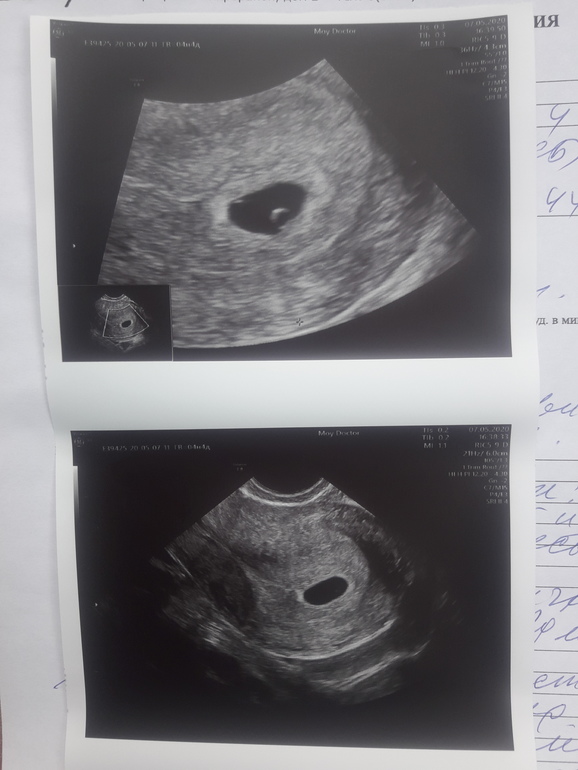

В этот же день побежала на узи, плодное яйцо в полости матки...